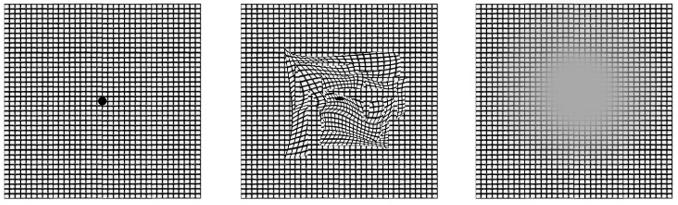

Degeneración macular asociado con la edad

Se caracteriza por cambios degenerativos progresivos en la retina central (mácula) → discapacidad visual.

CLASIFICACIÓN

Forma seca (90%)

También conocida como no exudativa o atrófica

DIAGNÓSTICO

Metamorfopsias (distorsión de línea) Discromatopsias

Forma seca:

♦ Deterioro visual lento y progresivo (generalmente durante décadas)

♦ FO: DRUSA (retinol)

Forma húmeda (10%)

También conocida como exudativa o neovascular

Forma húmeda:

♦ Pérdida brusca de visión

♦ FO: neovasos coroide – retina

♦ Angiografía de fluorescencia: neovascularización y exudación en la región macular

REJILLA DE AMSLER: detección de metamorfopsias y escotomas

a. Los ojos de una persona sana perciben una cuadrícula de líneas rectas

b. Si hay degeneración macular avanzada las líneas aparecen distorsionadas u onduladas (metamorfopsia).

c. También puede ocurrir un escotoma central

Las drusas son depósitos localizados de material rico en lípidos (fosfolípidos, grasas neutras) ubicados debajo del epitelio pigmentario.

Figura

relacionada con la edad. Gran hemorragia subretiniana (parcialmente intraretinianas) en la región macular. Este hallazgo ocurre principalmente en presencia de neovascularización coroideapigmentario.

a. b. c. Figura 56. Rejilla de Amsler Figura 57. Degeneración macular seca relacionada con la edad 58. Degeneración macular húmeda